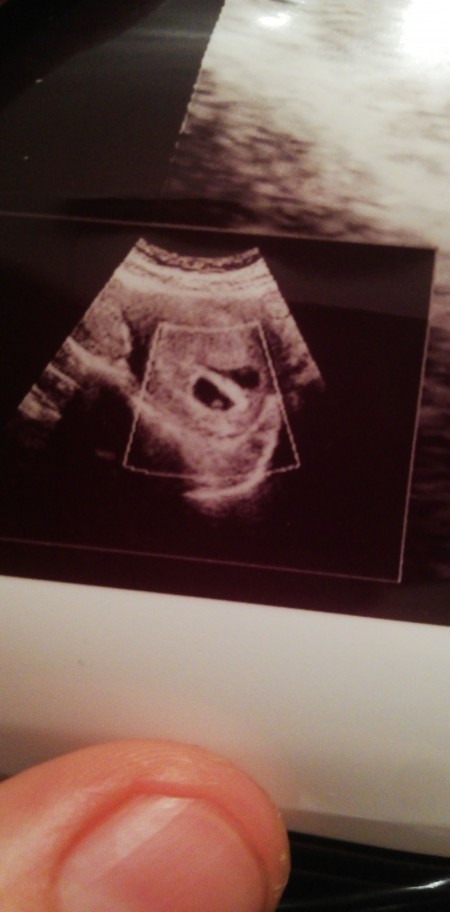

Kese Var Bebek Yok

Kese Var Bebek Yok.

6 0 da kese var bebek yok boyle olup sonradan bebegin kalp atisini duyan var mi hamilelik donemi genel